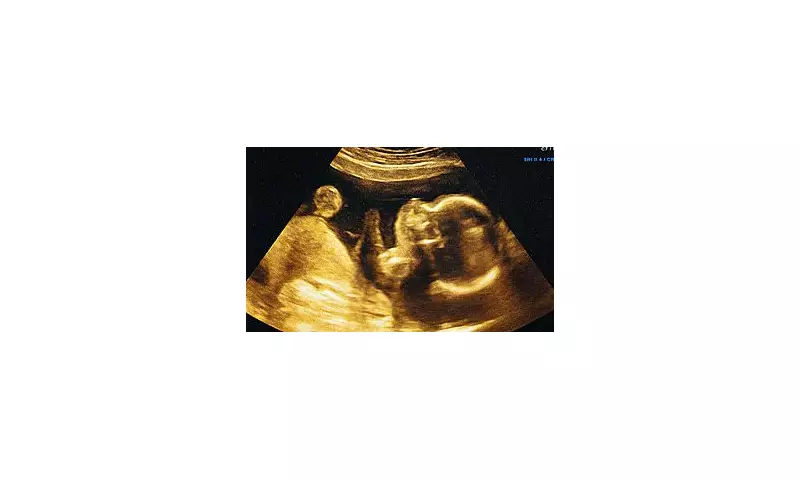

In a revolutionary leap for prenatal care, artificial intelligence (AI) has been trained to analyse ultrasound scans and predict a baby's due date with remarkable precision. This cutting-edge development could transform pregnancy management, offering expectant mothers and healthcare providers more accurate timelines than ever before.

Researchers have developed sophisticated algorithms capable of interpreting subtle patterns in ultrasound imagery that human clinicians might miss. By examining multiple parameters including fetal size, organ development and growth rates, the AI system can estimate gestational age with unprecedented accuracy.